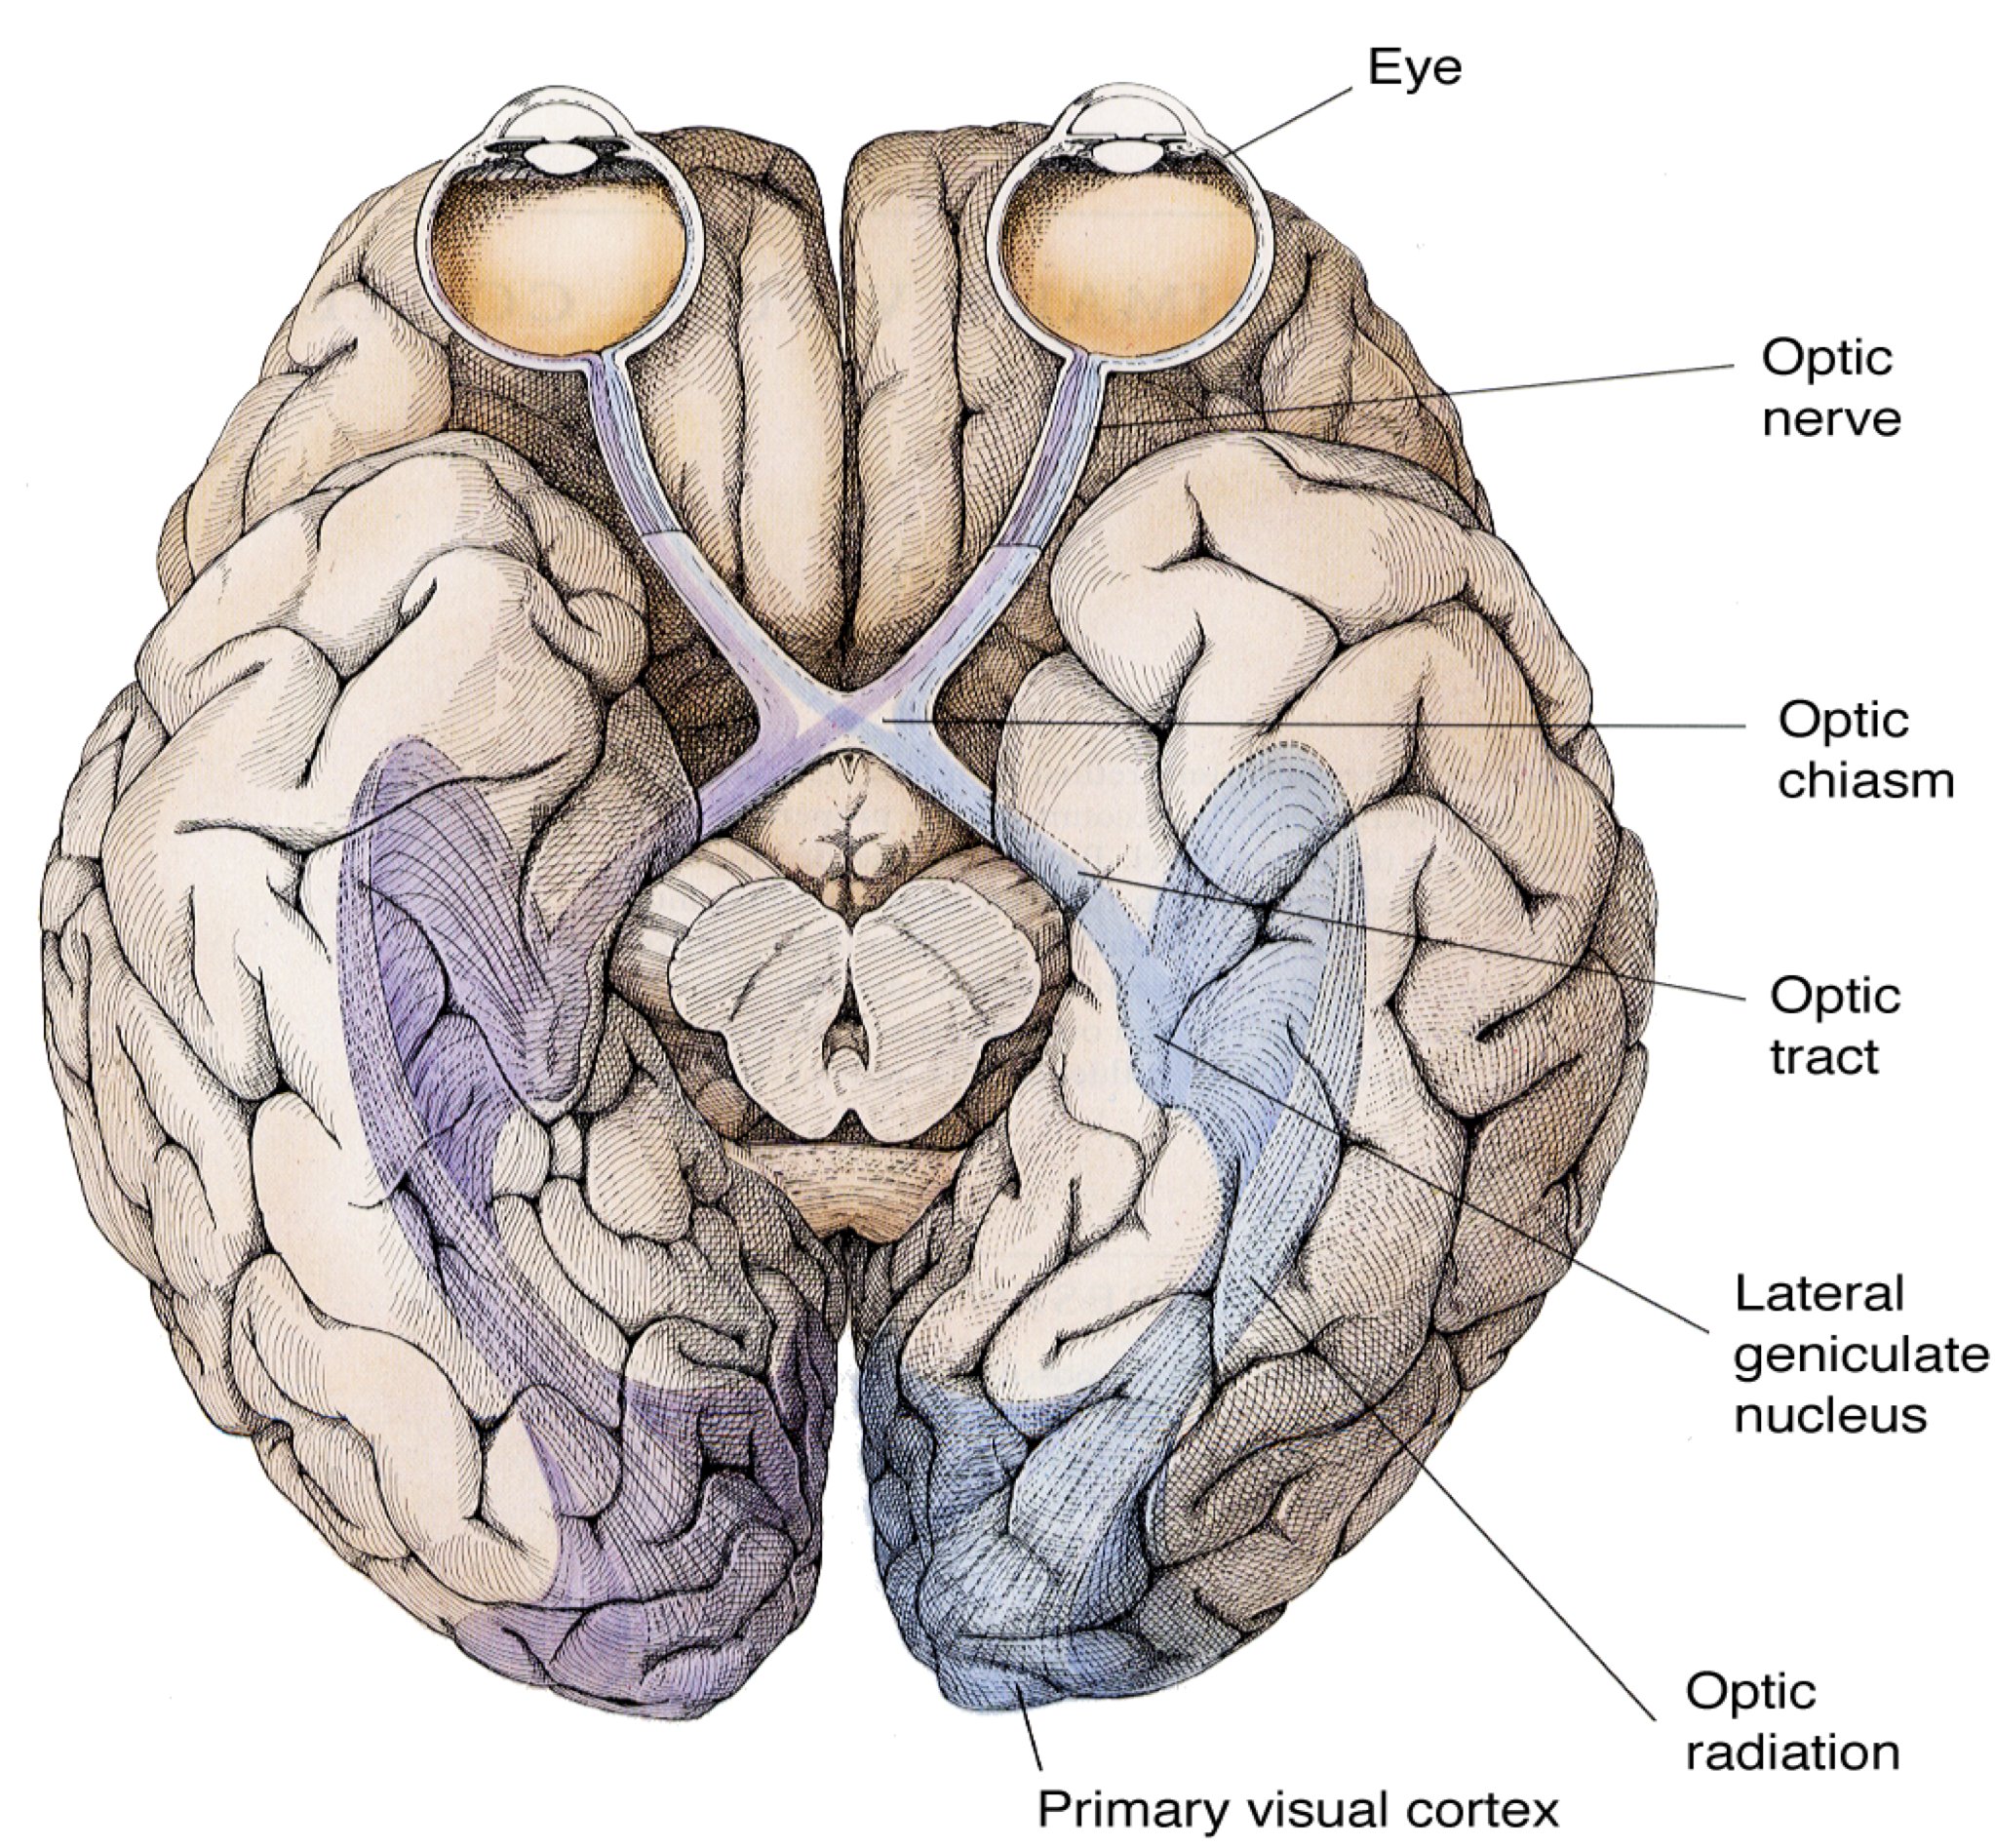

The visual pathway– retinotopy

Hubel, 1988 retina superior colliculus, dLGN, visual cortex

Neighboring retinal ganglion cells in the eye detect changes in contrast from similar portions of the visual field, thus forming a 2D map of visual space in the retina. This spatial representation of objects in the retina is then projected onto -->multiple down stream visual areas, so that maps of retinal topography, or retinotopy, are maintained at multiple levels in the visual system.

- At the optic chiasm, visual information from the two sides of the head cross

- In animals with eyes on the sides of the head, the entire visual field for each side is sent to the opposite side of the brain (to the tectum)

- In forward-looking animals, the visual image is split

- An object on the right side of the visual field is seen by both left hemi-retinae (but not by the right hemi-retinae). The optic nerves leave the retinae, and at the optic chiasm, the two left hemi-retinae projections go left, while the two right hemi-retinae go right

Projection to cortex

- The visual field is projected in a retinotopic fashion

- The right visual field is projected onto the left cortex, while the left visual field is represented on the right

- The region of the fovea, because of its high sensitivity and density of cones, is represented by a huge amount of the cortex